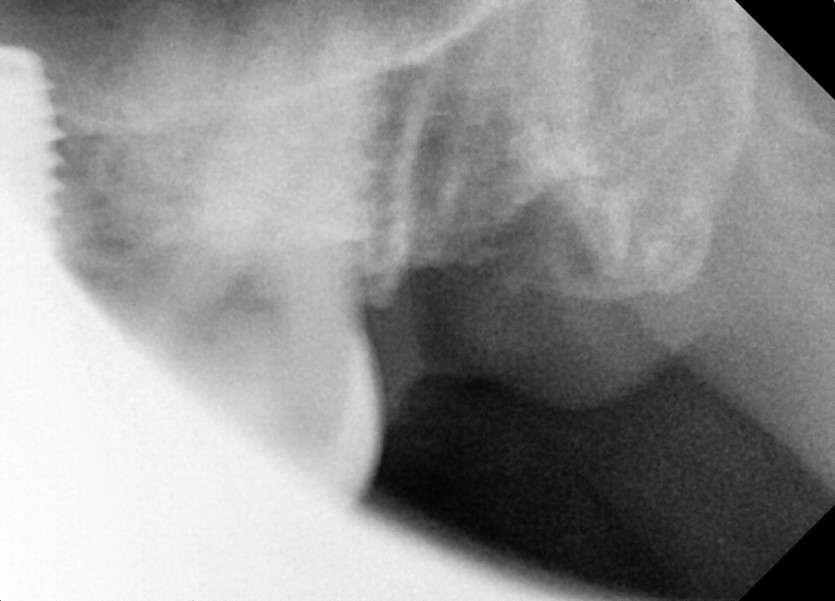

#28,38 사랑니 발치

구강 외과 전문의가 당일 발치했습니다.